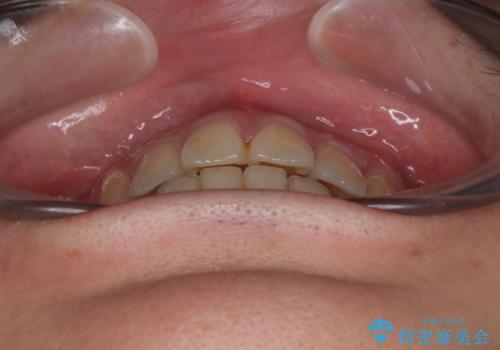

- 高校生の時に行った抜歯矯正の後戻りを気にして来院された患者様です。

インビザラインでの治療を希望されていて、デコボコの程度が中等度であり、安価なパッケージにて対応可能と判断されたため、インビザライン・モデレートを用いて矯正治療を行うこととしました。